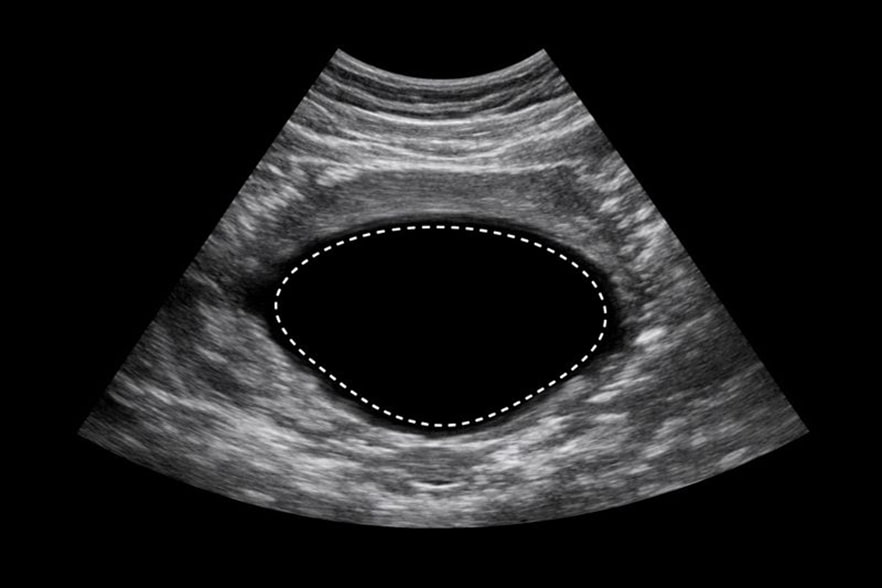

УЗИ мочевого пузыря с определением остаточной мочи — это ультразвуковой метод, направленный на измерение объема жидкости, которая сохраняется в полости органа после завершения акта мочеиспускания. Полученные показатели позволяют судить о полноте опорожнения и функциональных возможностях органа.

УЗИ мочевого пузыря с определением остаточной мочи дает возможность оценивать функциональное состояние органа после мочеиспускания. Специалист анализирует оставшееся количество жидкости и сопоставляет показатели с установленными нормативами.

УЗИ мочевого пузыря с определением остаточной мочи проводится в несколько последовательных этапов. Сначала выполняется первичное сканирование при наполненном органе, что позволяет оценить его форму и объем.

Затем проводится повторное исследование после мочеиспускания. Такая процедура позволяет точно определить разницу показателей и сделать выводы о функциональном состоянии. Обследование не вызывает дискомфорта и хорошо переносится.